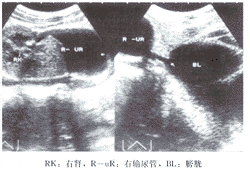

超声诊断先天性肾旋转反常并巨输尿管及其开口位置异常1例

患者男, 14岁 ......